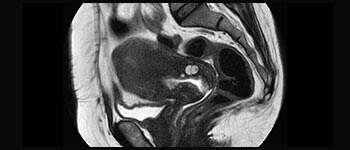

Mw. Silvia Schiffer, directeur en senior radioloog bij Radiologie Schiffer in Duitsland, deelt haar ervaringen met het Ingenia Prodiva 1.5T MR-systeem.

Lees wat de eerste gebruikers van Ingenia Prodiva 1.5T zeggen over hun ervaringen met het systeem en welke invloed het systeem heeft op hun afdeling Medische Beeldvorming.